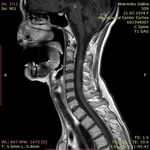

МРТ